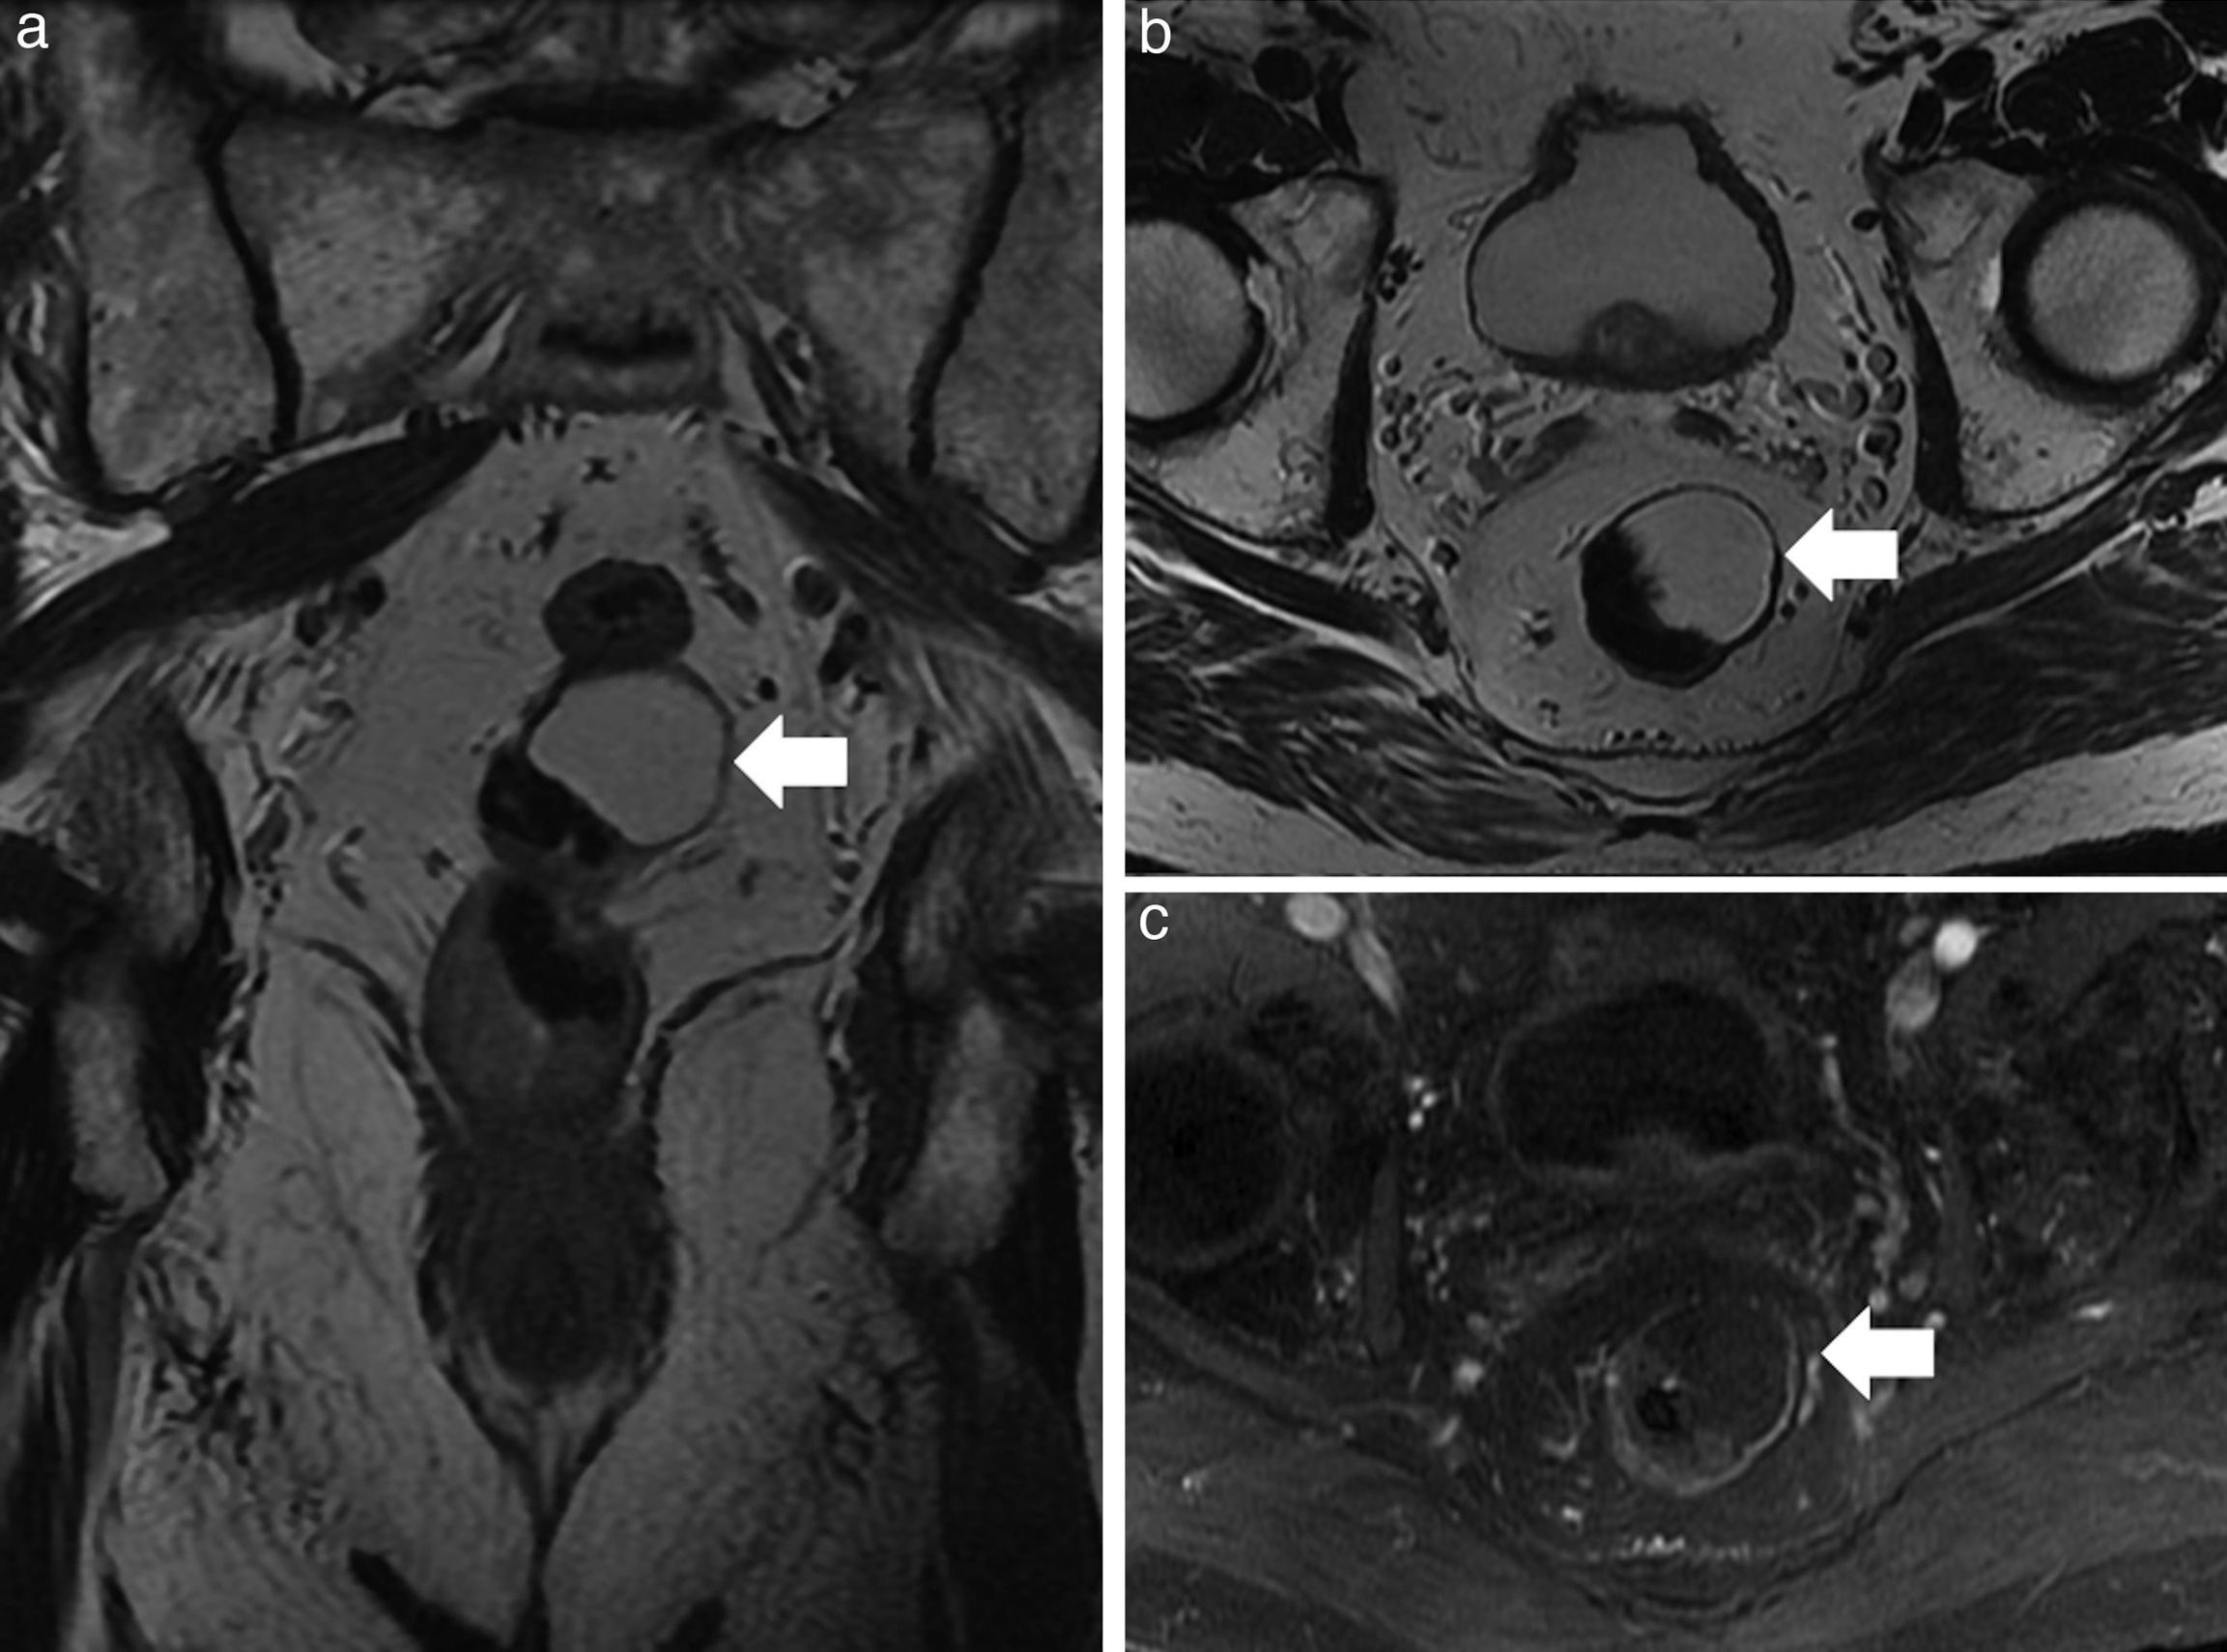

Benign anorectal disease comprises a broad group of processes with very diverse origins; these processes may be congenital or acquired as well as inflammatory or tumor related. However, benign anorectal disease has received less attention in the scientific literature than malignant disease. We present an image-based review of the most common benign diseases of the anus and rectum. In this first part, we review the anatomy of the region and provide a brief description of the peculiarities of the high resolution protocol that we use with 3.0 T MRI. We go on to describe the most common benign anorectal tumors and developmental cystic lesions, together with their differential diagnoses, as well as congenital and acquired anomalies of the anorectal sphincter complex.